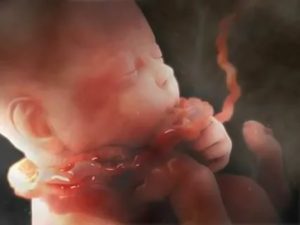

Пуповина также называется пупочным канатиком и представляет собой образование, которое напоминает спирально скрученный шнур. Она имеет следующие характеристики:

Когда пуповина петлями ложиться вокруг плода, данное явление называют обвитием. Согласно классификации данной патологии, обвитие происходит только вокруг одной части тела плода — шеи, но при этом в зависимости от числа витков обвитие может быть одно-, двух- и многократным.

Пуповина, помимо плаценты, является главным «связующим звеном» между матерью и ребенком. Через пуповину плод получает кислород, все необходимые питательные вещества, витамины и микроэлементы. Полностью формируется пуповина примерно к 14 неделе беременности и в норме ее длина составляет около 40-60 сантиметров.

Пуповина (пупочный канатик) – основное связующее звено между организмом мамы и малыша, в ее состав входит соединительная ткань, пупочная вена и 2 артерии.

По сосудам к младенцу поступает кровь с кислородом и питательными веществами, затем кровь течет обратно, удаляет продукты жизнедеятельности.

Пуповина– это особый орган, который соединяет плаценту с плодом. Формирование пуповины начинается с 11 недель. К моменту родов ее толщина достигает 2 см: в это время она состоит из двух артерий и одной вены.

Артерии несут к плаценте кровь плода, насыщенную углекислым газом и продуктами обмена веществ. А через вену, кровь, обогащенная кислородом и питательными веществами, поступает к ребенку. Сосуды пуповины окружены особым веществом – вартоновым студнем.

Эта желеобразная субстанция предохраняет их от сдавливания.